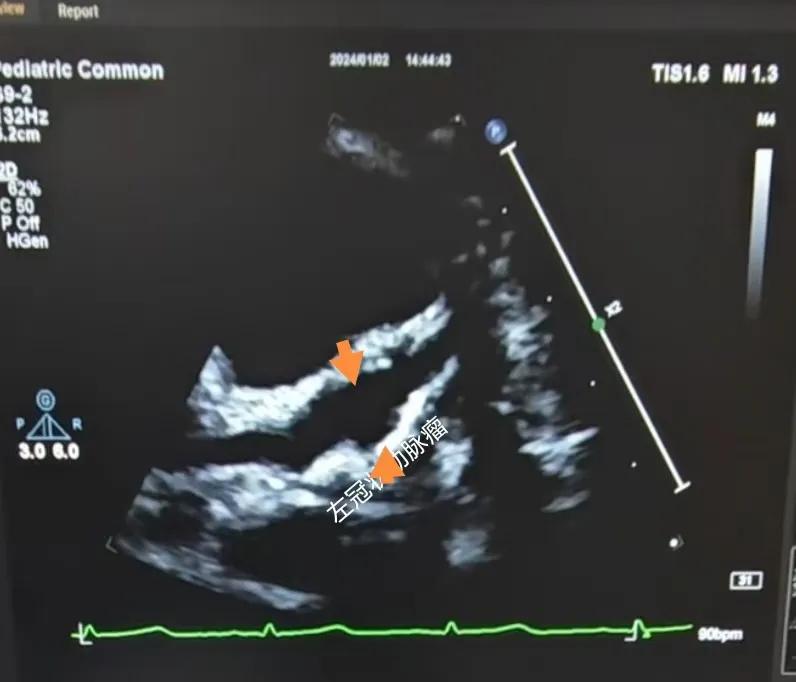

(川崎病患兒:增寬的右側冠狀動脈)

(川崎病患兒:左冠狀動脈瘤)